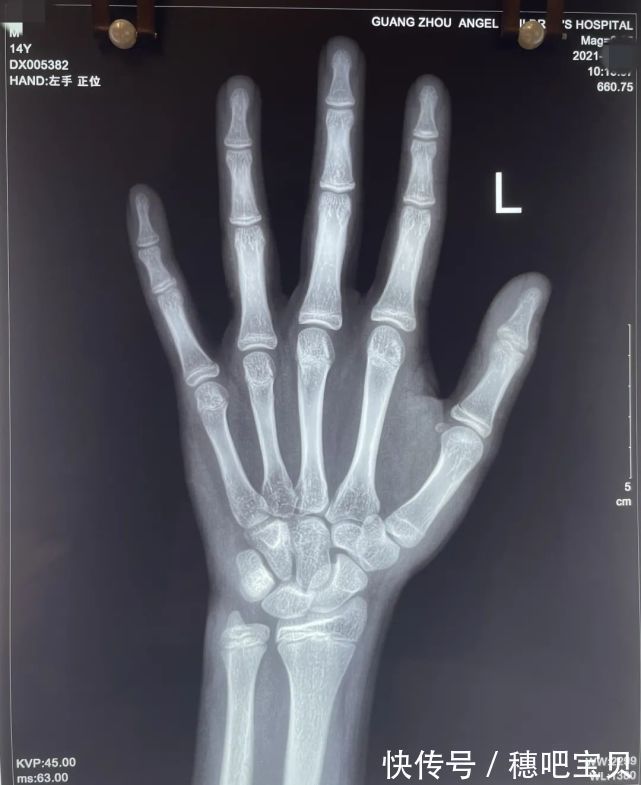

小天的骨龄已经15.5岁了,由于孩子过早发育,导致手部骨骺线快要闭合,腿部骨骺线还有少许空隙,长高空间较小。

文章插图

(小天骨龄片检查结果)